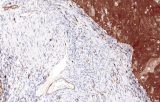

L’immunoistochimica (IHC) con anticorpi primari CE/IVD è essenziale per una diagnosi e classificazione accurata sia delle malignità ginecologiche che mammarie. Questi anticorpi consentono la rilevazione precisa di marcatori tumorali e proteine cellulari, supportando la diagnosi differenziale e guidando strategie terapeutiche personalizzate.

Studi recenti sottolineano il valore diagnostico delle proteine del complesso SWI/SNF, in particolare ARID1B, nell’identificazione di malignità ginecologiche dedifferenziate e indifferenziate – tumori aggressivi con prognosi sfavorevole. L’IHC di ARID1B offre alta specificità e viene sempre più integrata nei pannelli diagnostici per migliorare la precisione. Pannelli con marcatori aggiuntivi supportano anche la differenziazione dei sarcomi uterini, aumentando l’accuratezza diagnostica. Evidenze emergenti suggeriscono che ARID1B potrebbe rappresentare un potenziale bersaglio terapeutico nel carcinoma ovarico a cellule chiare, sebbene le applicazioni cliniche rimangano in fase di ricerca.